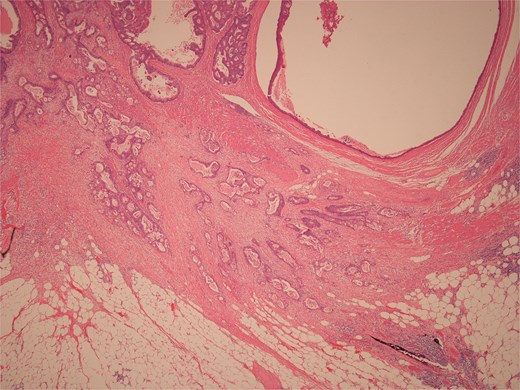

Histopathological examination of surgical specimens revealed three distinct neoplasms: (i) invasive colonic adenocarcinoma (Figs 4 and 5), (ii) jejunal NET (Figs 6 and 7), and (iii) small-lymphocytic lymphoma (Figs 8 and 9). Morphological assessment supported by immunohistochemical profiling confirmed each represented an independent primary, with no evidence of a shared clonal origin. The findings were subsequently reviewed at the Multidisciplinary Meeting alongside Oncology and Haematology specialists, and adjuvant single-agent chemotherapy was initiated, with planned surveillance of the indolent lymphoma.

High power view of colonic adenocarcinoma showing complex glandular structures lined by epithelial cells with high grade atypia, and lumina containing necrotic debris, invading beyond the mucosa.